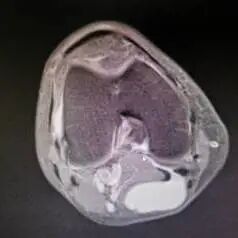

选择何种方式可依据术前核磁共振的检查情况决定。核磁共振显示腘窝囊肿与关节腔相通,腓肠肌间隔血管、神经的囊肿时建议的手术方式为前内外侧入路处理膝关节腔病变+单后内或双后内入路切除囊肿。如下图所示:

对于如何选择单后内或双后内入路切除囊肿,一可以通过术前膝关节核磁共振的检查了解囊肿的大小、位置及是否存在分隔来决定;二可以通过术中视野及操作决定;由于单后内入路切除术,观察入路位于前方,由于胫骨平台及内侧腓肠肌的遮挡,视野存在一定的盲区,对于囊肿相对较小,基本位于膝关节线水平、无分隔的囊肿,可以选择该入路进行手术;而对于囊肿较大、囊肿上下边界距离关节线比较远的囊肿,为了较好的将囊壁较完全的切除通常选择双后内入路切除囊肿。

如下图所示,核磁共振显示腘窝囊肿与关节腔不相通,与血管、神经相邻的囊肿,可选择开放手术,降低神经、血管损伤的风险。